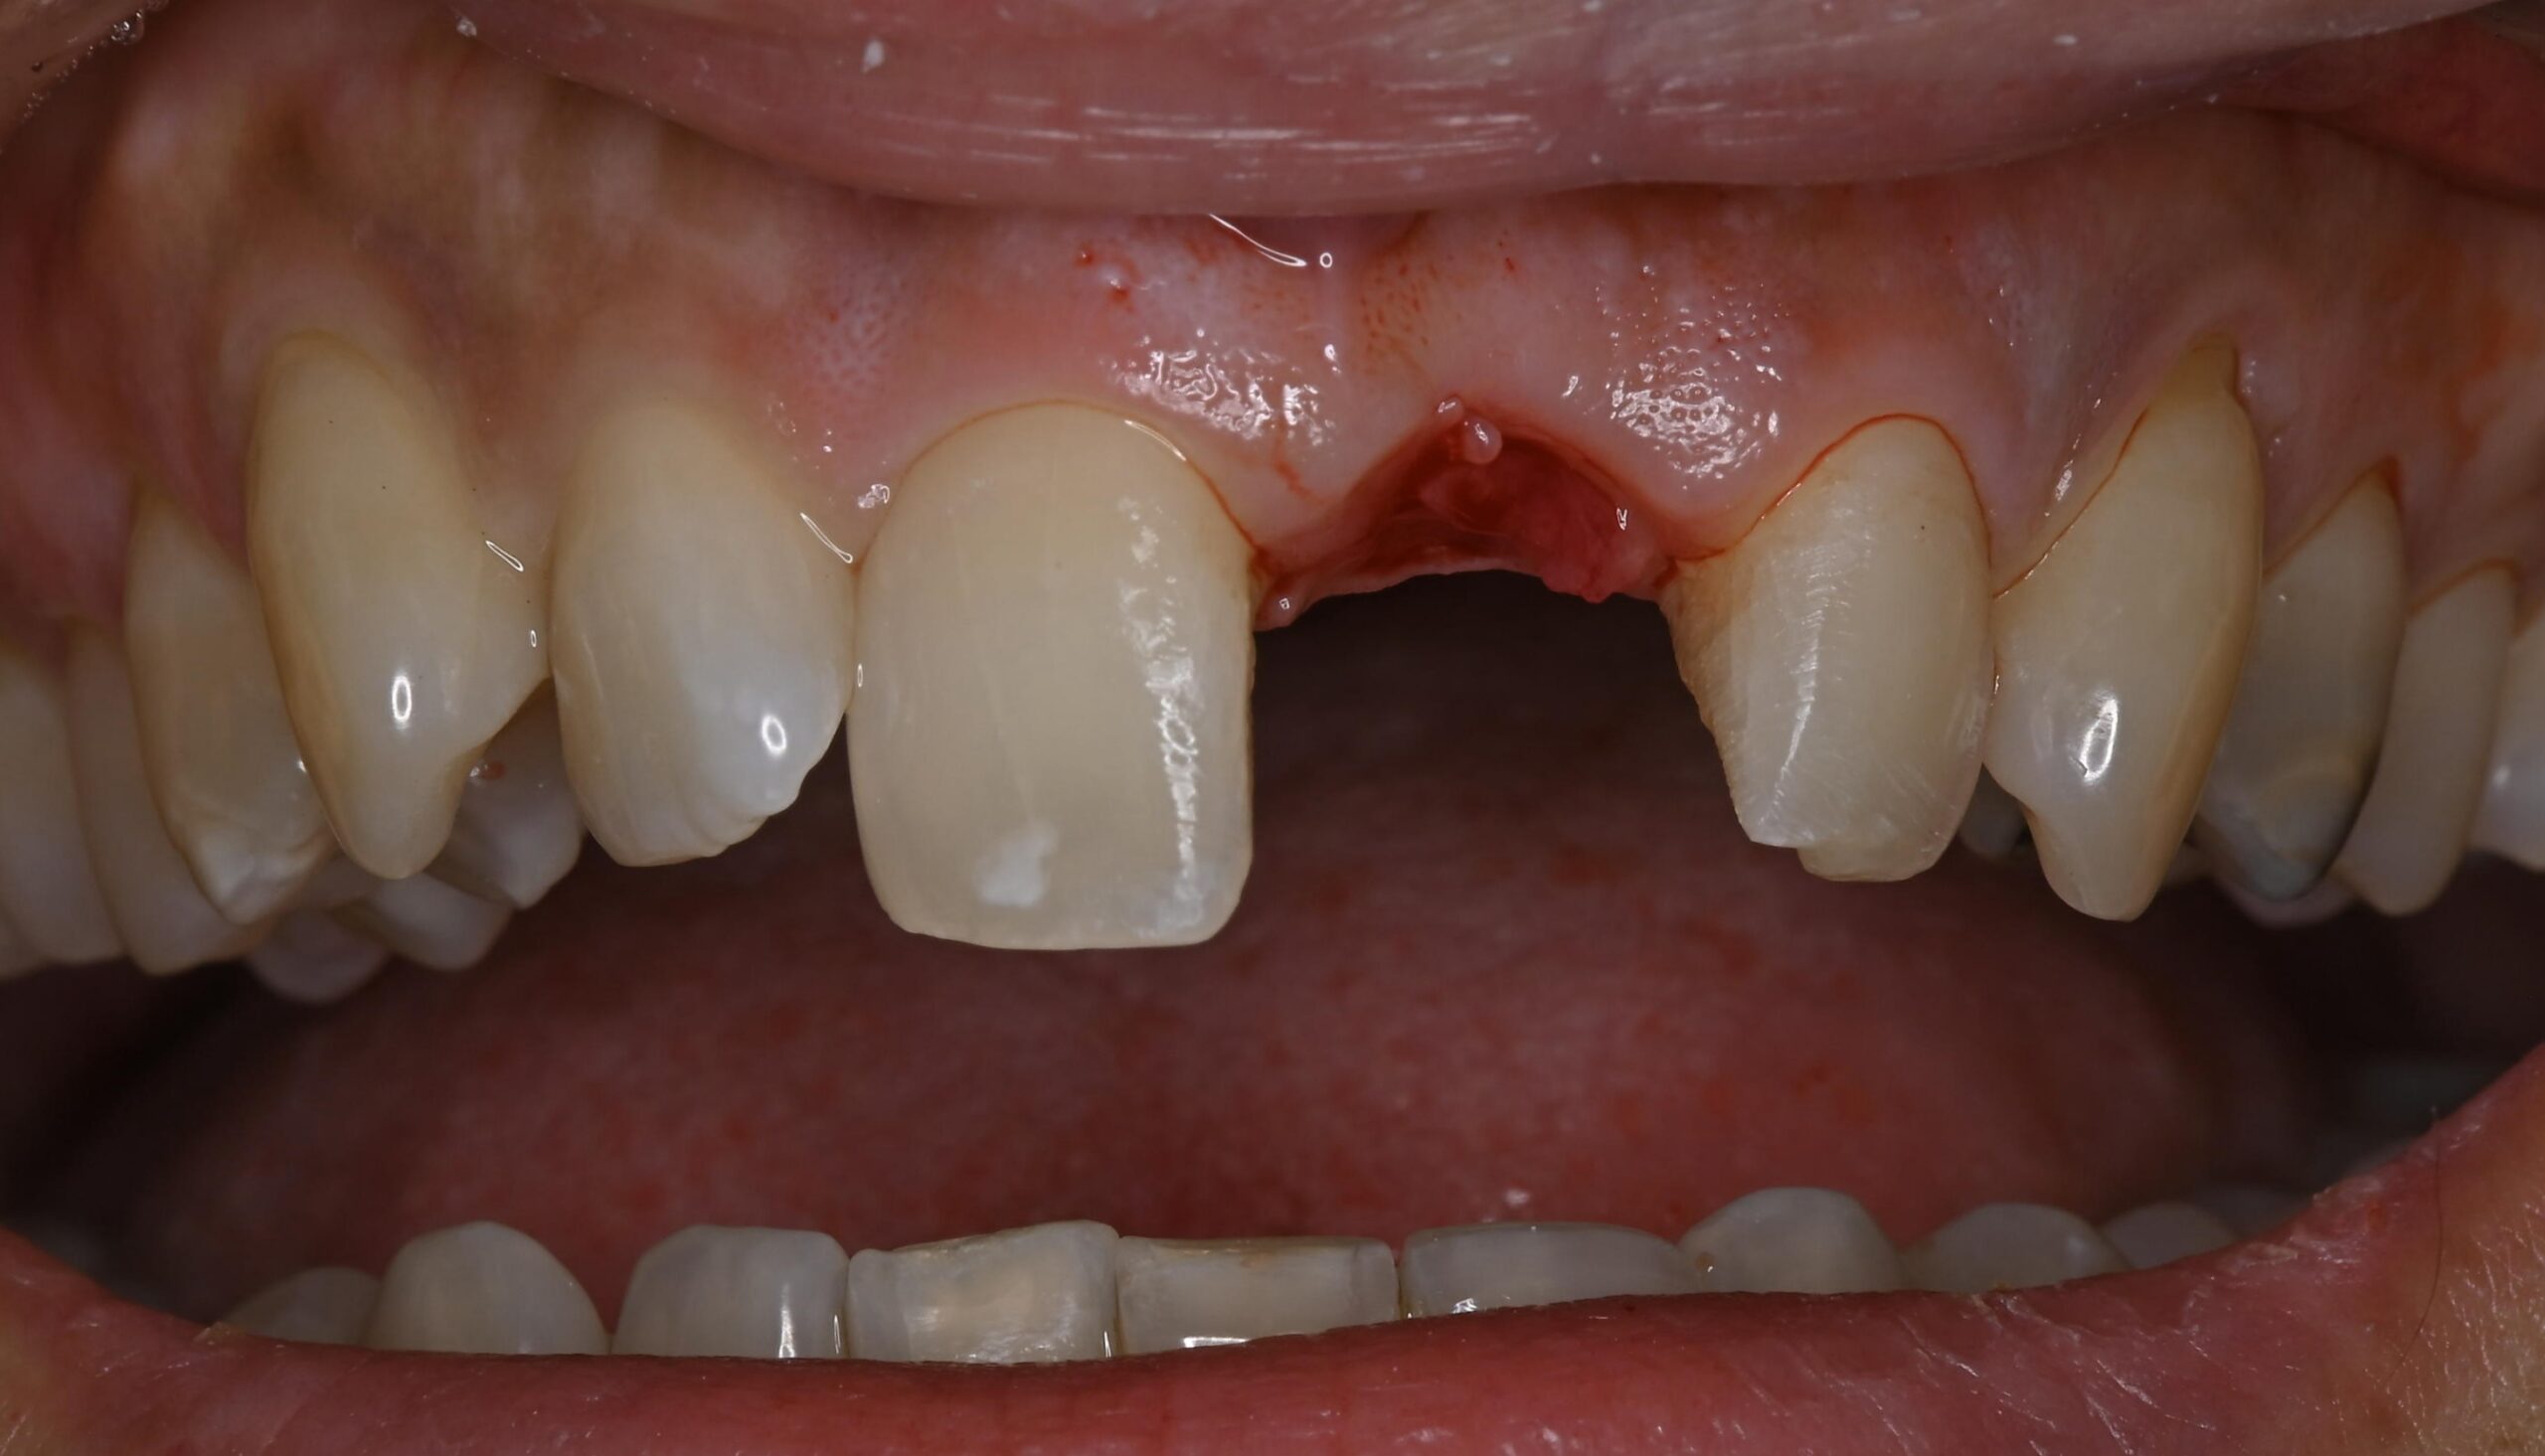

ジルコニアブリッジの症例

Before

After

左上1番を他院にて抜歯し、仮歯をボンドで固定された状態で来院されました。

歯を失ったところをブリッジで治す計画をたて、審美的な補綴を目指すためにホワイトニングから行いました。

最終的にジルコニアのブリッジを接着しました。

担当歯科医師:平沼 佳朗

治療期間・回数

約4回

費用

¥462,000

リスク・副作用

ごく稀にジルコニアの先端が割れることがあります。